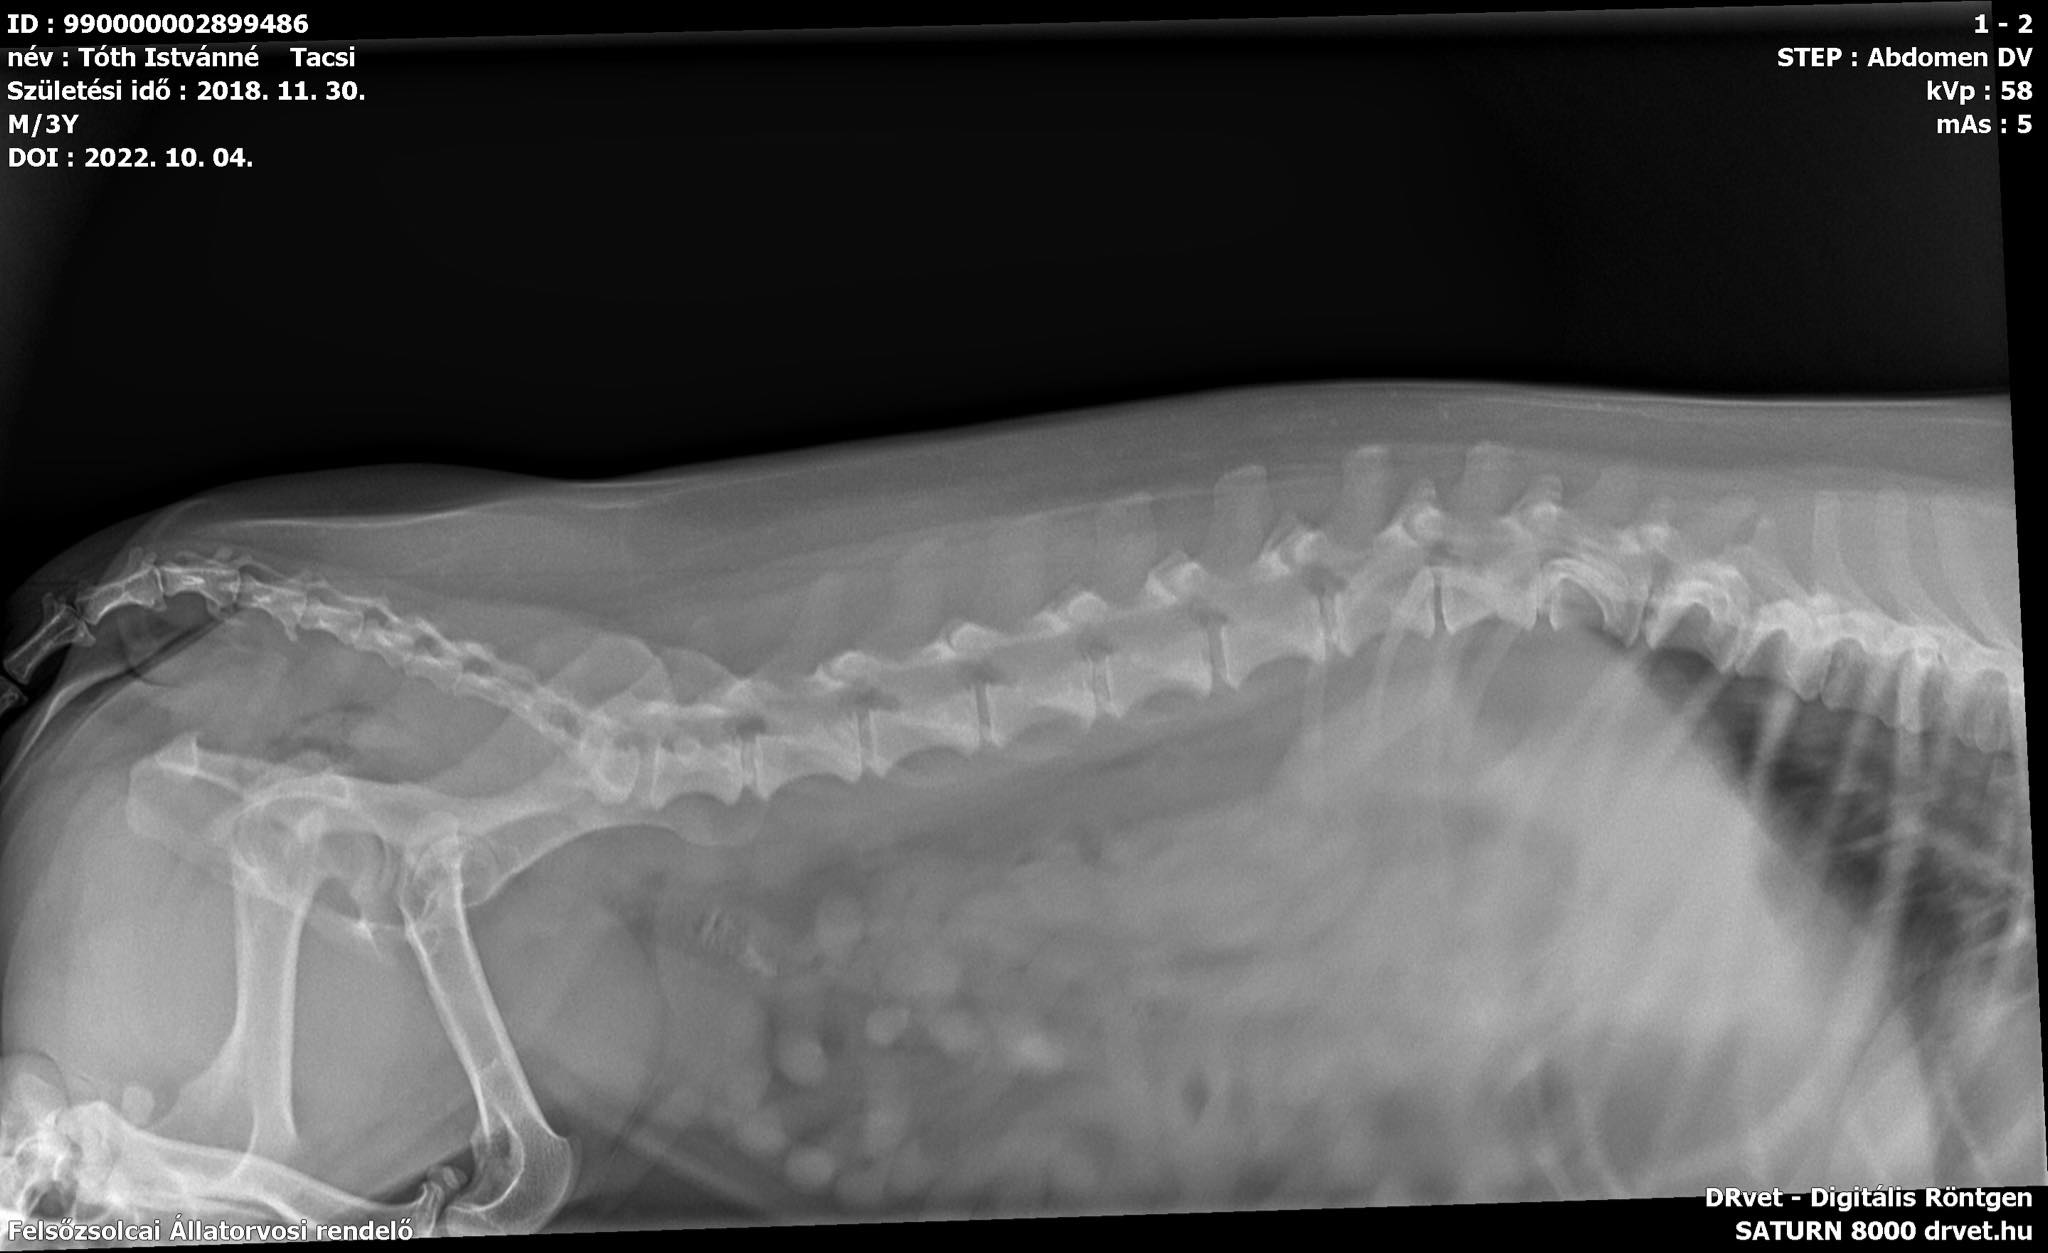

Tacsi kutyánkat 3 éves korában tacskóbénulással diagnosztizálták, egyik napról a másikra nem tudott lábra állni, ezért orvoshoz vittük. Tacskóbénulást állapitottak meg, és MRI vizsgálatot és műtétet javasoltak.